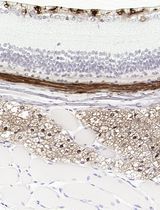

采用 Davidson 固定液和黑色素漂白法优化小鼠眼组织切片的免疫组化染色

Anne Nathalie Longakit [...] Catherine D. Van Raamsdonk

2025年11月20日 1624 阅读